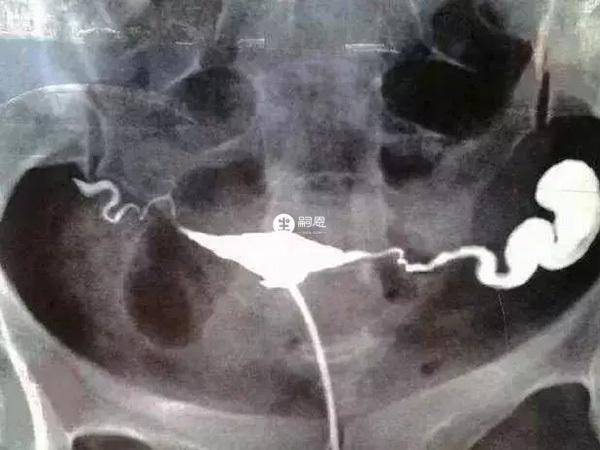

3、输卵管积水

输卵管积水造影片子的表现是是一侧或双侧输卵管远端增粗和膨大,呈“腊肠状”,这是因为输卵管远端粘连不通导致输卵管内造影剂不能溢出,所以输卵管积水的前提是输卵管本身就不通。

一侧输卵管积水

输卵管积水有可修复性和不能修复性两种,其区别在于显影边缘的清晰度、是否有毛玻璃影。而输卵管积水对于自然怀孕或试管婴儿都会有影响,建议备孕或试管胚胎移植前先处理积水。